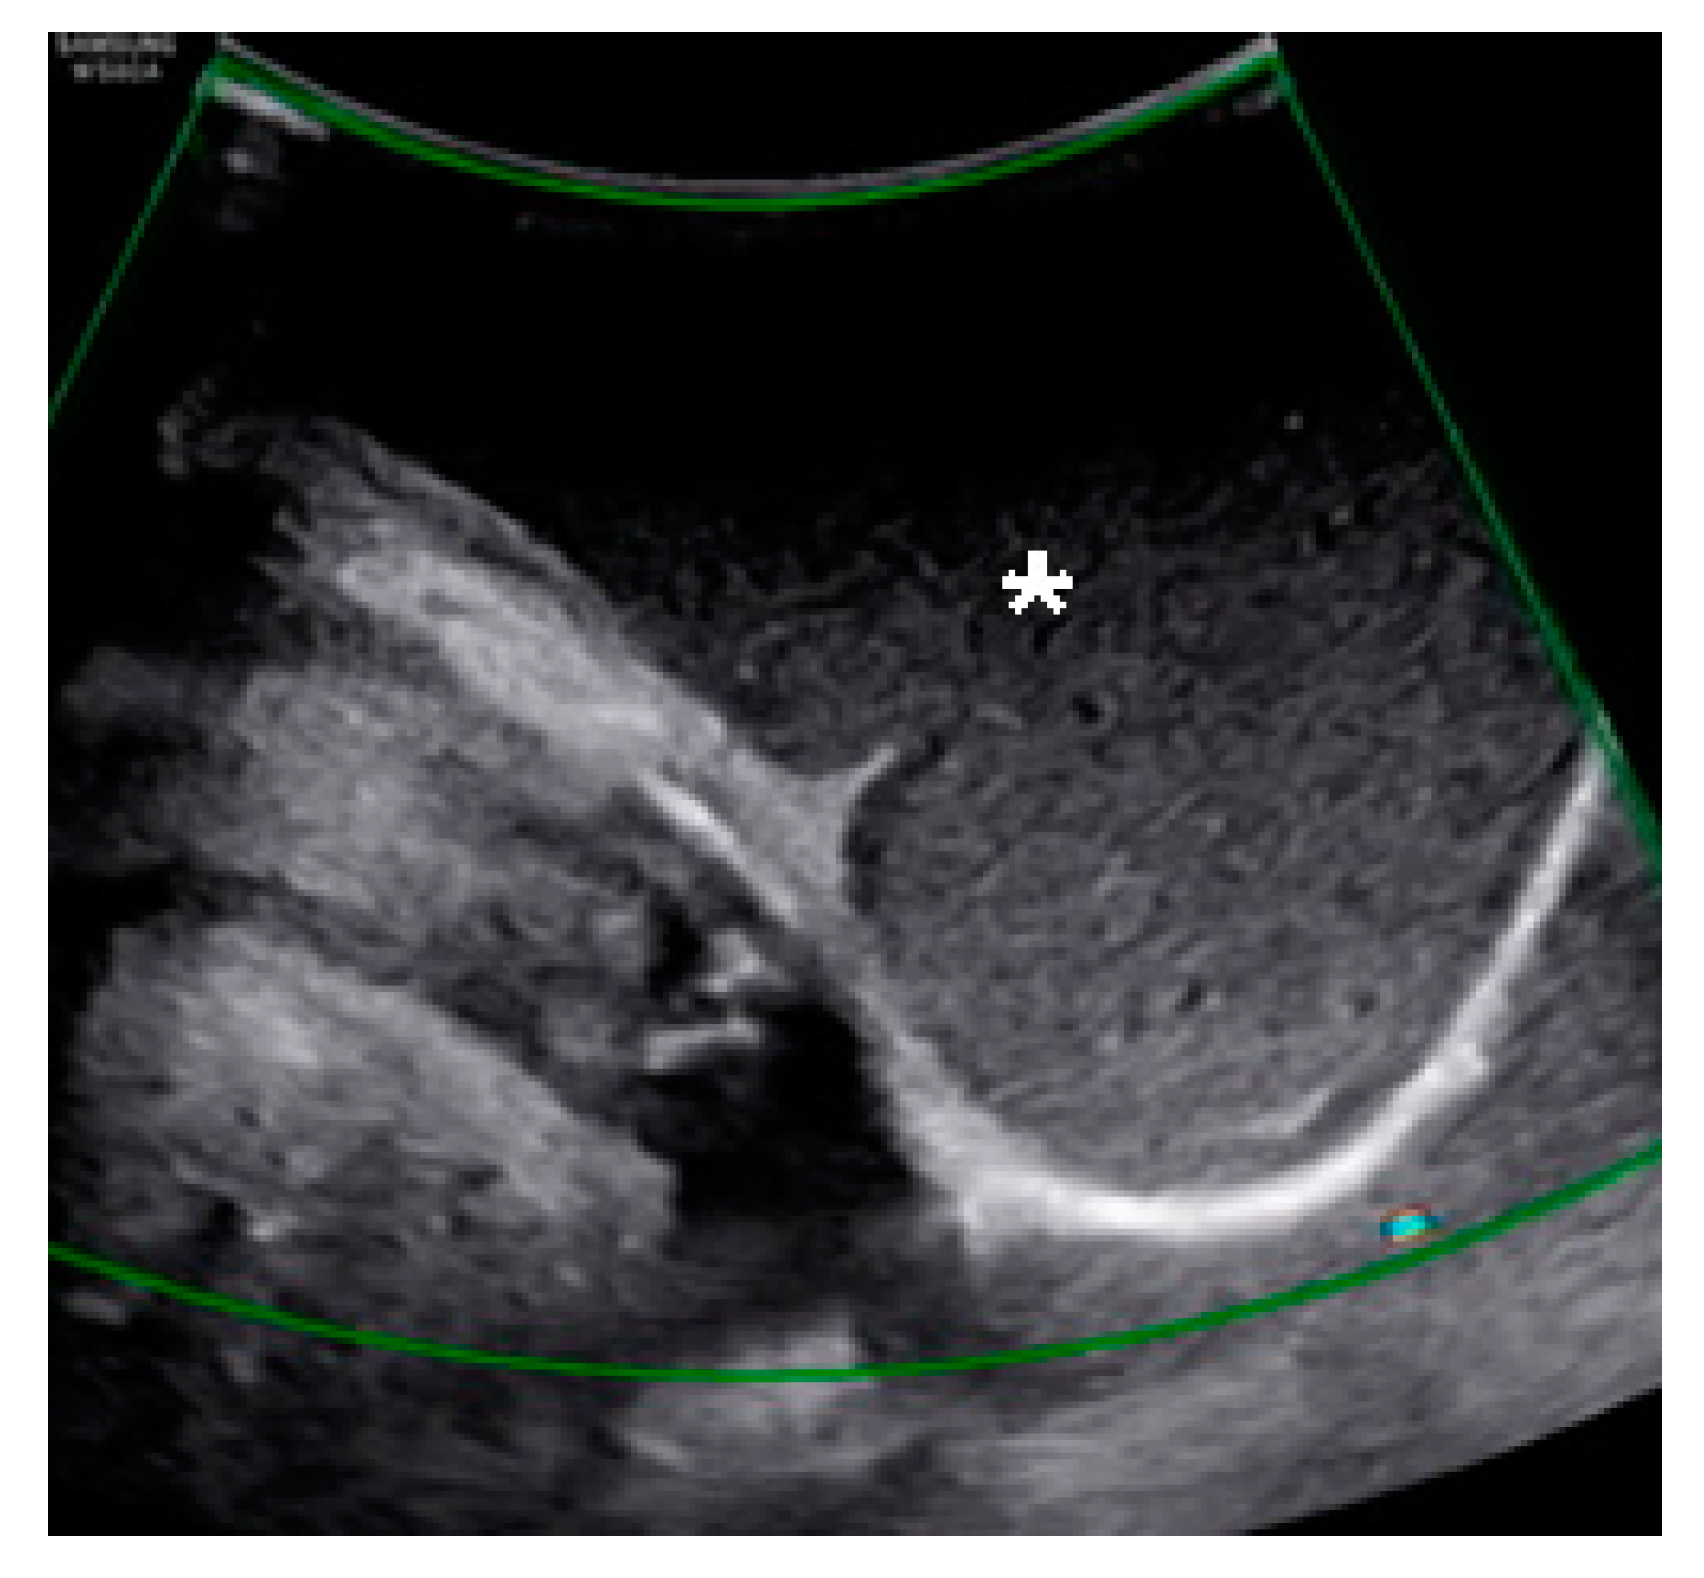

A Huge Hemorrhagic Epidermoid Cyst of the Perineum with Hypoechoic Semisolid Ultrasonographic Feature Mimicking Scar Endometriosis

Nam, G.; Lee, S.R.; Eum, H.R.; Kim, S.H.; Chae, H.D.; Kim, G.J. A Huge Hemorrhagic Epidermoid Cyst of the Perineum with Hypoechoic Semisolid Ultrasonographic Feature Mimicking Scar Endometriosis. Medicina 2021, 57, 276. https://doi.org/10.3390/medicina57030276